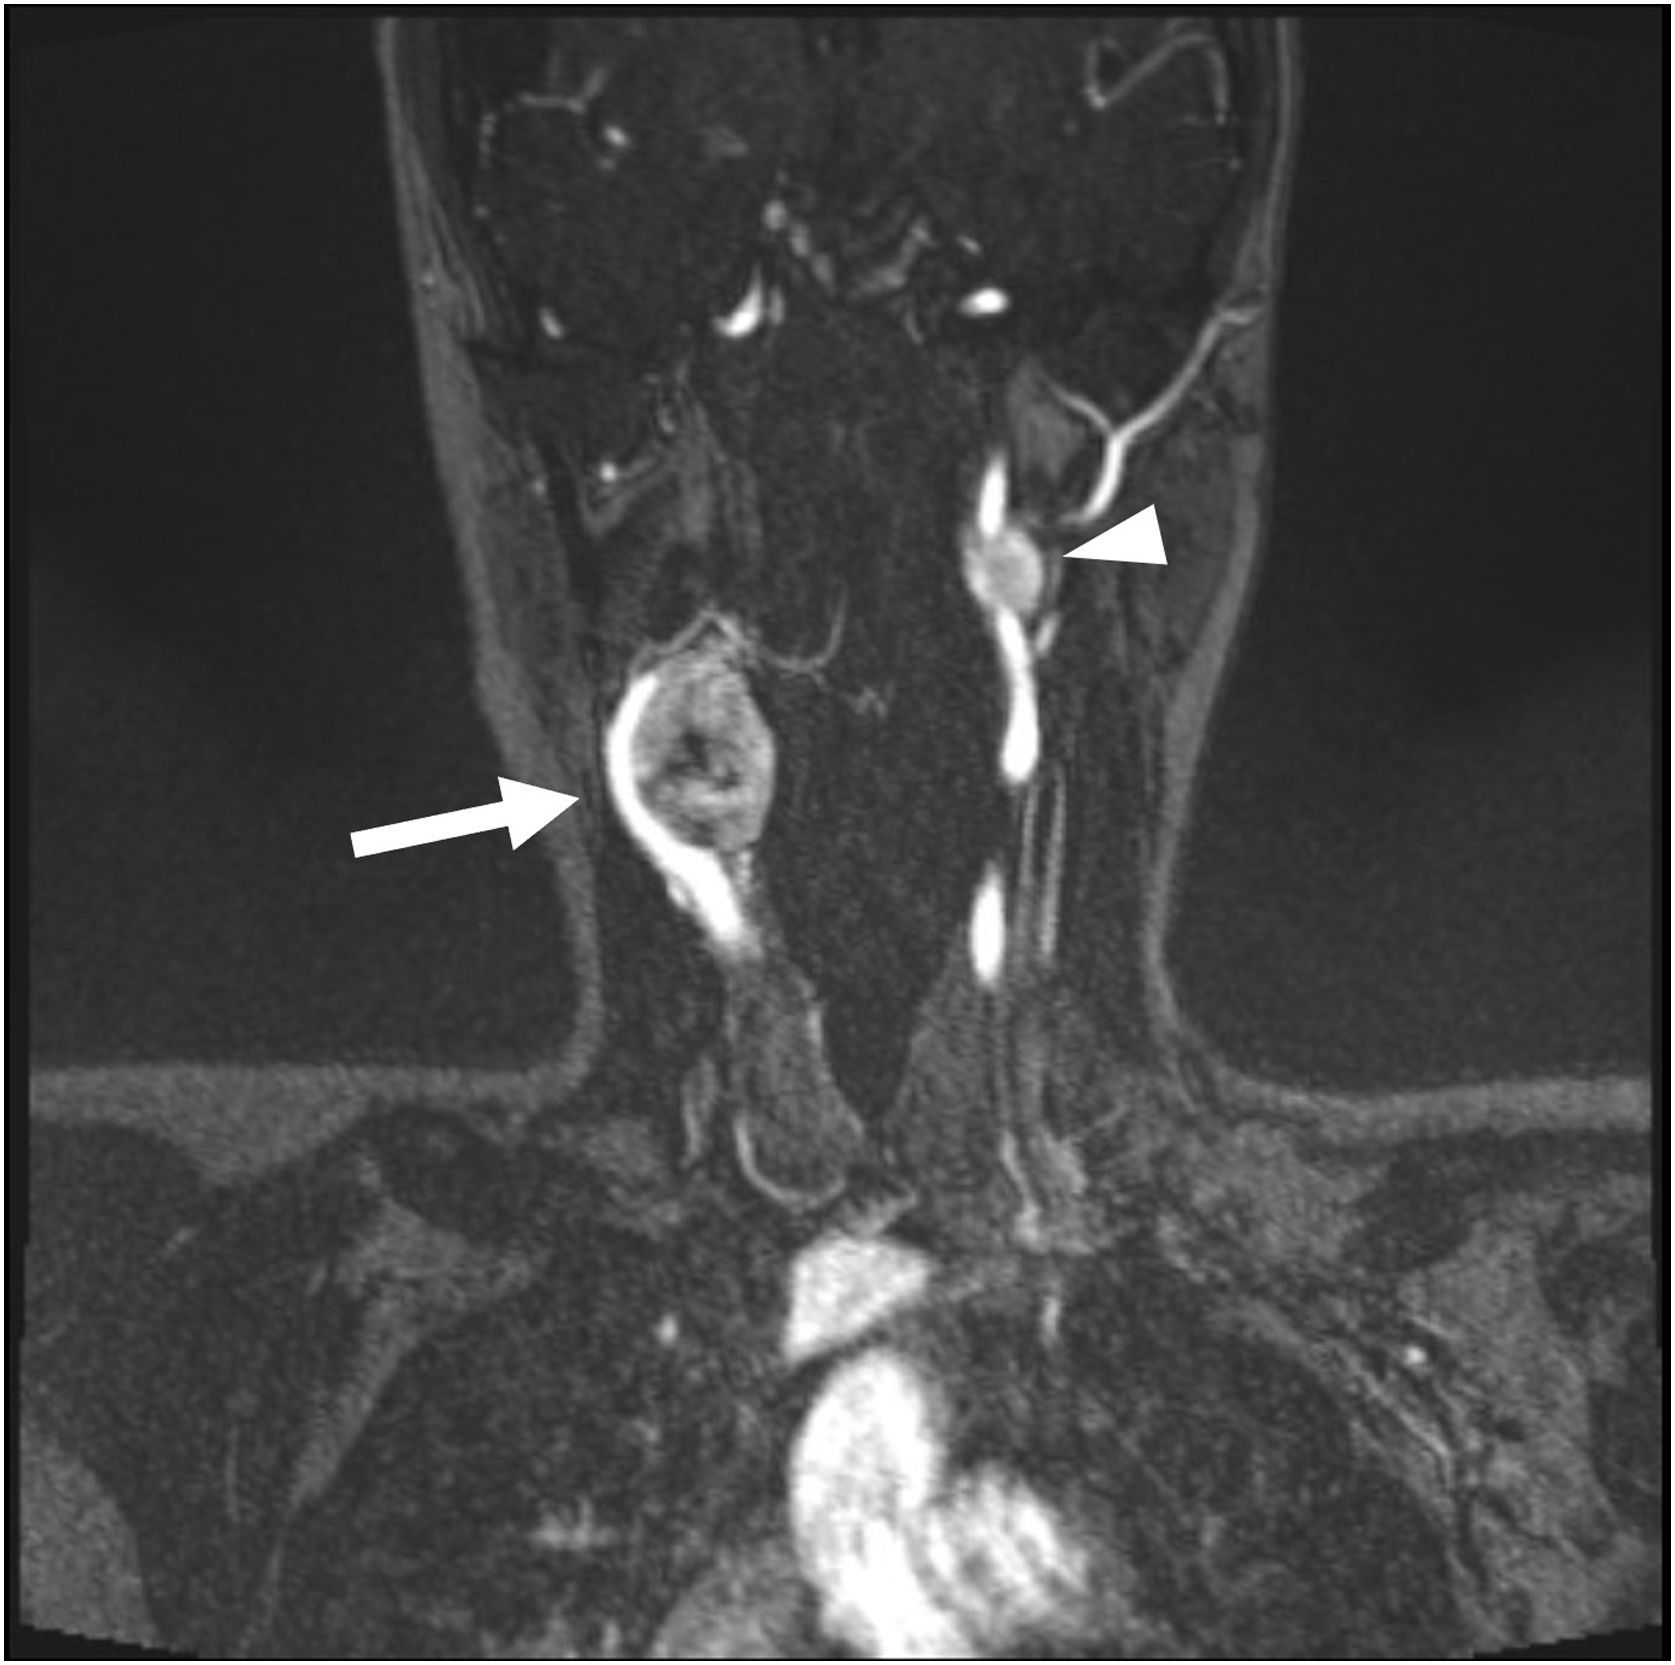

A rare case of synchronous multicentric paragangliomas detected using [⁶⁸Ga]Ga-DOTATATE PET/CT

Un raro caso de paragangliomas multicéntricos sincrónicos detectado mediante PET/TC con [⁶⁸Ga]Ga-DOTATATE